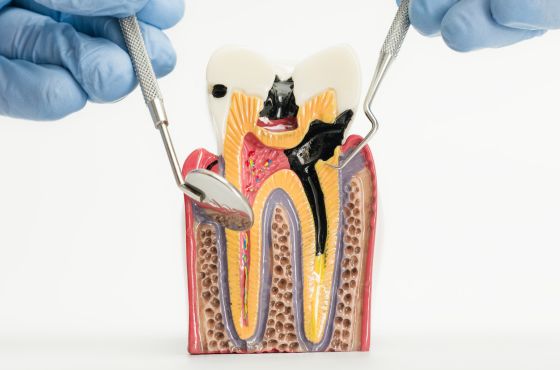

Las caries se originan cuando las bacterias de la boca descomponen azúcares de los alimentos y producen ácidos que dañan el esmalte dental. Si el daño alcanza la pulpa del diente, donde se encuentran nervios y vasos sanguíneos, puede formarse un absceso dental. En este punto, la infección puede propagarse más allá del diente.